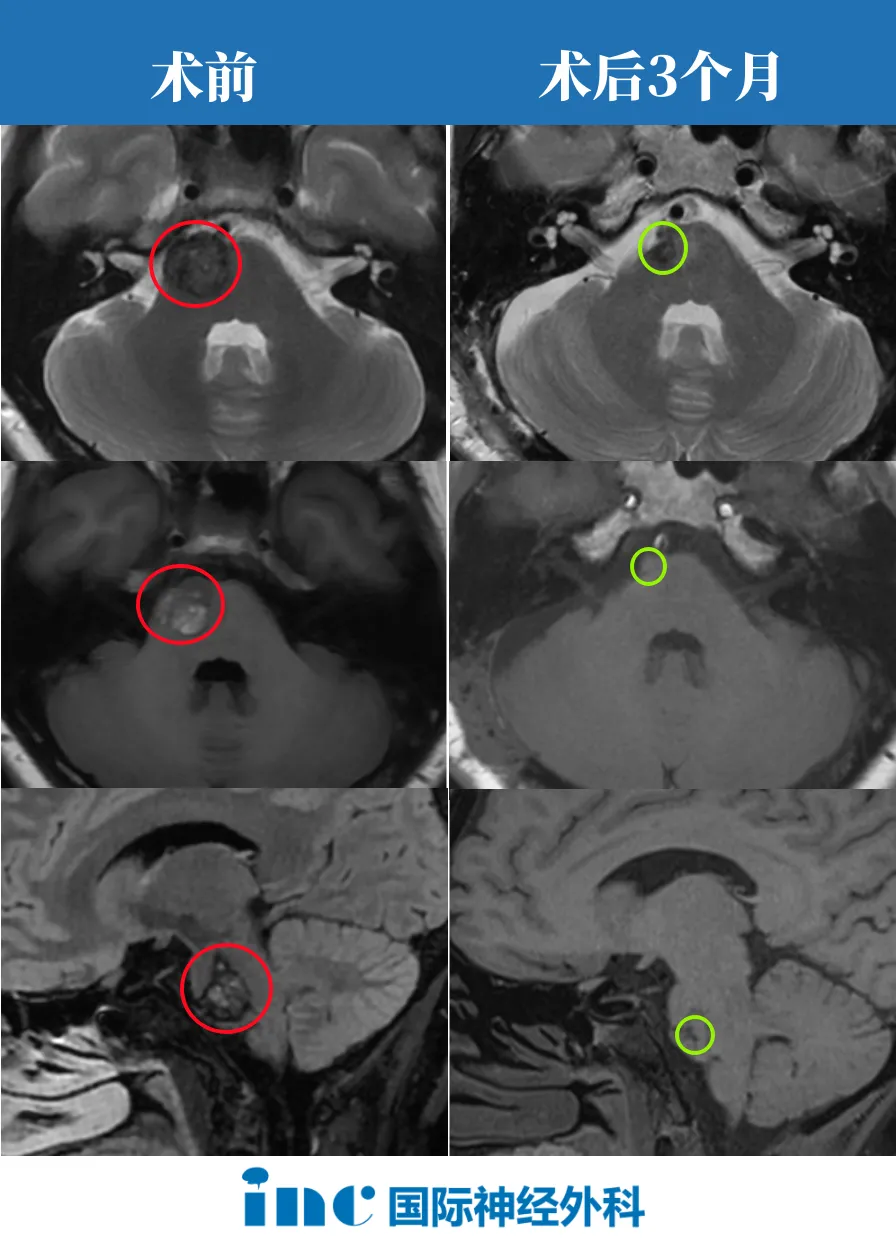

术后3个月时随访:“海绵状血管瘤被切除了,没有残瘤。”

最新影像显示手术后1年多,手术完全切除了脑桥内先前的出血性海绵状血管瘤。这是一个非常好的结果!!病人应该快乐地正常生活!